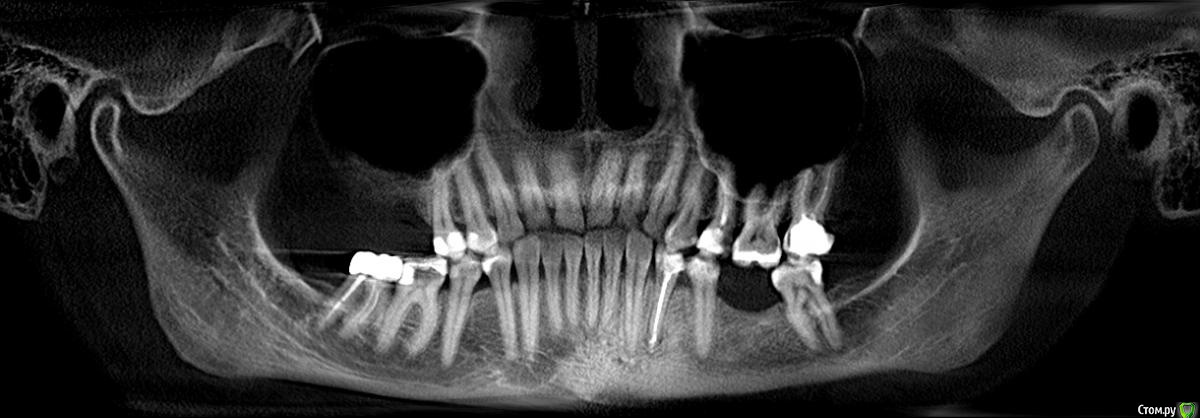

Ирина2706 Опубликовано 31 июля, 2017 Поделиться Опубликовано 31 июля, 2017 Добрый день, Ситуация такая, на верхнем правом 6 стояла коронка со штифтом, зуб начал беспокоить,на приеме оказалось ,что киста, перфорация.Зуб долго пытались спасти, но в итоге удалили 3 месяца назад, с планами поставить имплант. Лунка после удаления заживает хорошо, Но!!!! Меня постоянно беспокоят не сильные боли жжение , то в скуле, то в носу, переодически опухает небо . Была у лора, вылечили все, что было можно. Вернулась к стоматологу, сделали КТ. Стоматолог сказал, что все хорошо и может быть невралгия, назначил уколы. Направил на консультацию к терапевту по поводу верхней правой 5, сказав, что пломба большая и проблема может быть из-за нее. Терапевт сейчас в отпуске.Но смотря дома КТ, если смотреть с внутренней стороны нашла какую то точку, может ли это быть пломбировочным материалом или осколком? или еще чем то? На что еще надо обратить внимание. Получается, что врачи проблем не видят, а я постоянно мучаюсь.Что может быть? Что показывает КТ? Заранее спасибо откликнувшимся.Ссылка на КТ, разместила на нескольких.https://yadi.sk/d/sb6yYjV93LUrQA dropmefiles.com/S4Q8Y Ссылка на комментарий

Ирина2706 Опубликовано 1 августа, 2017 Автор Поделиться Опубликовано 1 августа, 2017 Удачи, напишите когда будут результаты. Была сегодня у терапевта, она посмотрела и сказала, что по снимку не видно, а КТ показало воспаление в корнях верхней пятерке, удалили нерв, положили лекарство. Жду 2 недели и на прием. Очень надеюсь, что это было моей проблемой, потому что лечить больше нечего ))) Ссылка на комментарий